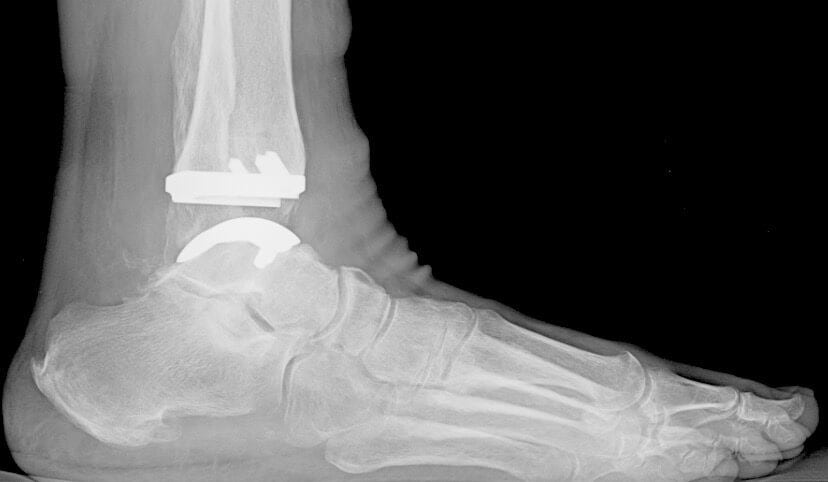

Сложность их конструкции обусловлена анатомическим строением голеностопного сустава, разнообразием осуществляемых функций. При создании всех моделей учитывались статико-динамические нагрузки, составляющие 3-13% массы тела. При конструировании тотальных имплантатов используются следующие элементы:

- округленные металлические пластины, защищающие поверхность таранной кости;

- металлические пластины для закрытия части большой берцовой кости;

- подвижное ядро из высокомолекулярного полиэтилена.

Такой способ хирургического вмешательства считается щадящим, так как сохраняется значительное количество суставных структур. Ранее при проведении операции могли использоваться длинные стержни. Теперь крепление пластин таранной кости осуществляется штифтами для плотного анатомического облегания костных поверхностей имплантационным покрытием. При его изготовлении применяется особый пористый материал, способствующий прорастанию сосудов и тканей. Это обеспечивает естественную и прочную фиксацию пластины. Короткий дюбель используется для крепления нижней защитной пластины, а вот ядро не закрепляется вовсе. Оно предназначено для обеспечения плавного скольжения между верхней и нижней металлическими пластинами. Верхний элемент имеет ограничитель, предупреждающий смещение ядра.

Установленный искусственный протез имеет те же функциональные характеристики, что и голеностопное сочленение. При его вживлении хирурги используют программное обеспечение для контроля баланса и фиксации имплантата. Это способствует длительному сроку службы протеза и отсутствию дискомфортных ощущений во время эксплуатации. Объем движений полностью восстанавливается, а за счет полимерных элементов в конструкции снижается трение, компенсируется нагрузка при соприкосновении собственных костных тканей пациента с имплантатом.